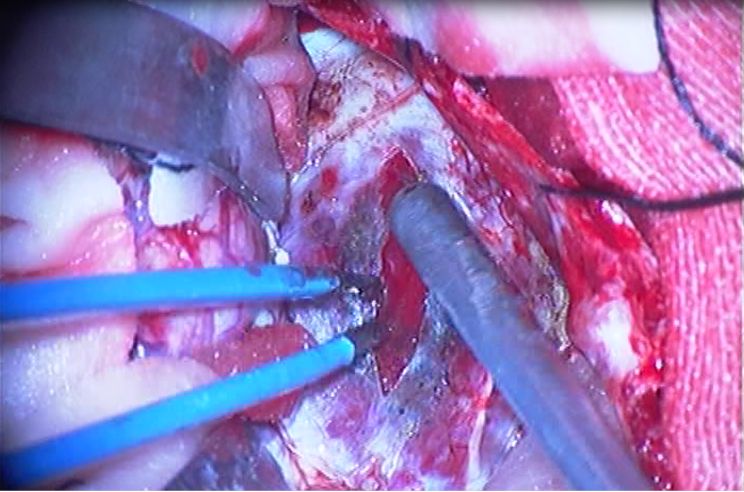

分离侧裂达中颅窝底,见海绵窦区巨大肿物,位于硬膜外海绵窦内,质韧,界清,包膜张力较高。

肿瘤主体在右侧海绵窦内,海绵窦外侧壁、上壁、后壁硬脑膜膨胀、变薄。

对于海绵窦内的海绵状血管瘤的切除,因其血供丰富,常整块切除。此例患者,经游离肿瘤四周,反复电灼肿瘤包膜,预使肿瘤体积缩小,但肿瘤体积巨大,无法整块切除。

术中决定分块切除。充分做好止血准备,反复灼烧、准备大量明胶卷以及液体明胶。

充分的电灼、止血,切除部分肿瘤以缩小其体积,扩大操作空间。

严格控制出血,应用明胶海绵填塞压迫和液体明胶交替使用以达到止血目的。